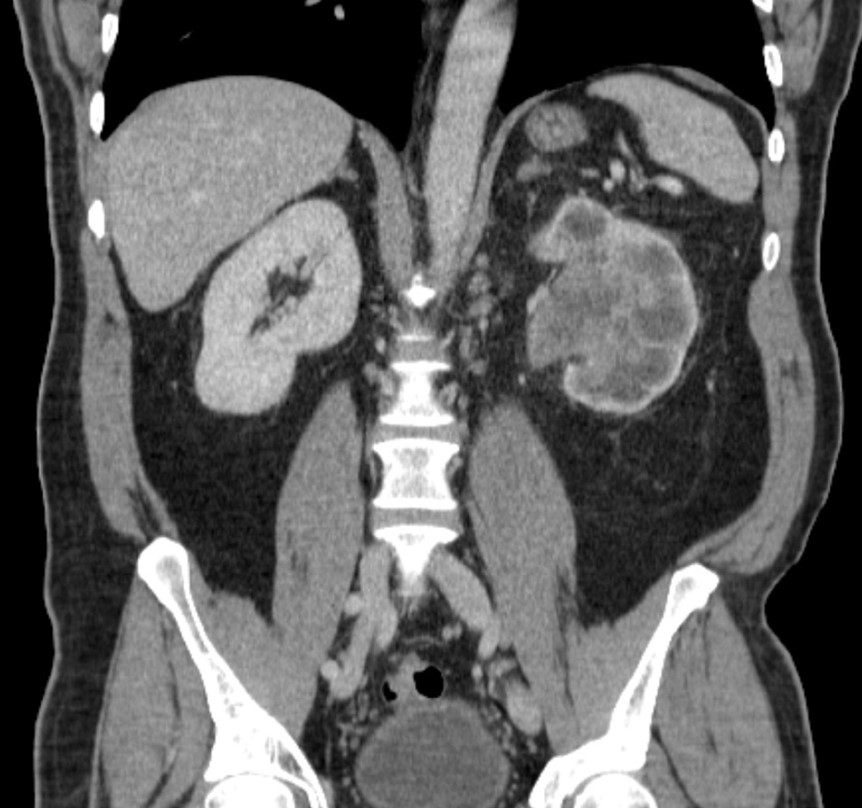

A 68-year-old male with no significant medical history presents for abdominal ultrasound.#ACRCaseinPoint

https://t.co/ZKGwIkx9MD